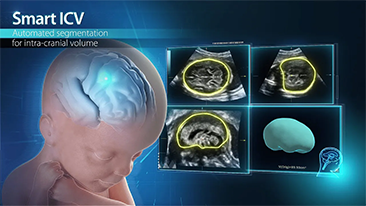

Con la tecnologĂa de la avanzada plataforma ZST+, las soluciones inteligentes completas de la serie Nuewa estĂĄn dise?adas especialmente para mejorar la salud de las mujeres durante el perĂodo previo al embarazo, el embarazo y la recuperaciĂłn en el posparto, con el fin de brindar diagnĂłsticos integrales y eficientes para enfrentar desafĂos clĂnicos cada vez mĂĄs exigentes.